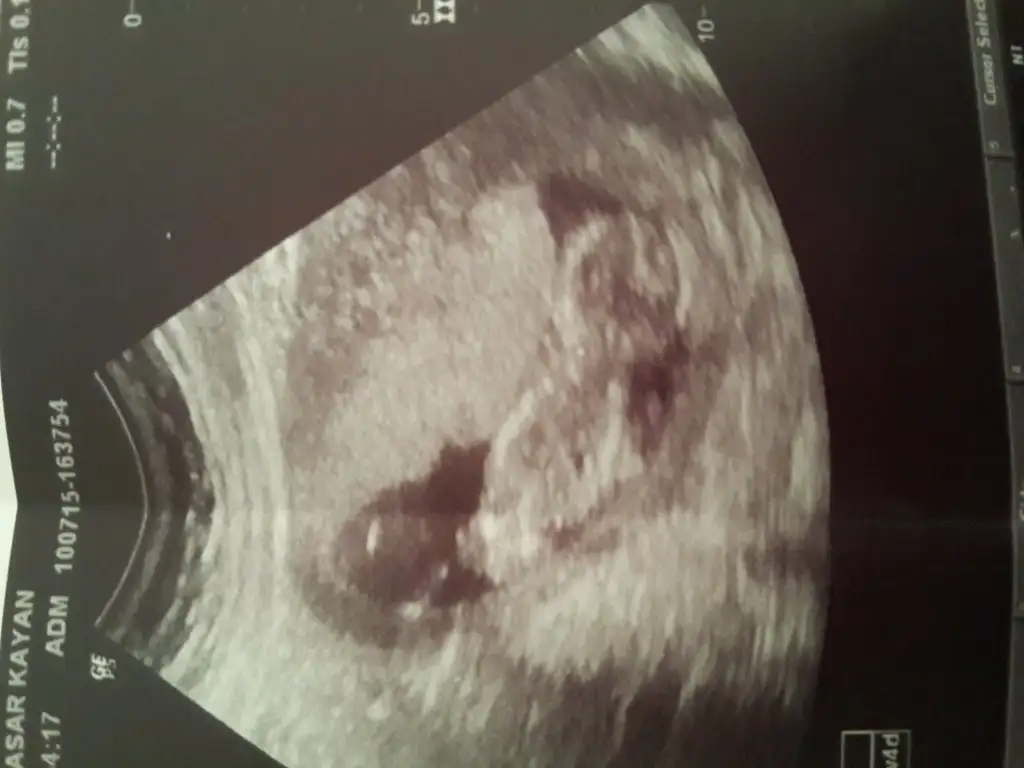

Slm kızlarrr bis geldik doktora gittik bugün fotomuzu aldık @msg38